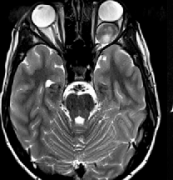

兒童視神經(jīng)膠質(zhì)瘤該如何治療才能保住視力?視神經(jīng)膠質(zhì)瘤(OPG)約占兒童腦腫瘤的3-5%。大約75%的腫瘤是在出生后的一個(gè)十年被診斷出來(lái)的,其中60%的患者在5歲前被診斷出來(lái);發(fā)病率...

視神經(jīng)膠質(zhì)瘤治愈率?小兒眼球震顫、不能視物要警惕!

什么是視神經(jīng)膠質(zhì)瘤?如何影像鑒別?視神經(jīng)膠質(zhì)瘤預(yù)后如何?一文帶你看懂...